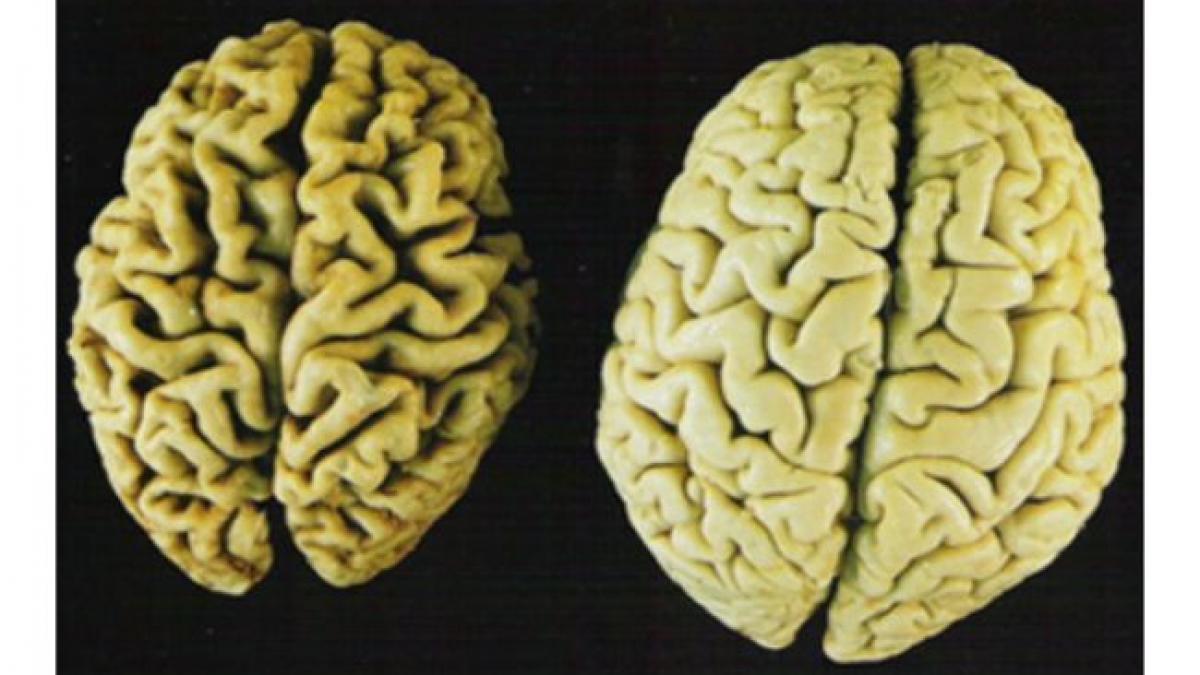

Celulele stem ar putea încetini evoluţia bolilor Alzheimer şi Parkinson, spune prof. dr. Dafin Mureşanu, preşedintele Societăţii Române de Neurologie, citat de Mediafax.

"Cercetătorii americani au un studiu avansat în privinţa utilizării celulelor ste, care a fost prezentat la Congresul Societăţii pentru Studiul Neuroprotecţiei, desfăşurat la Praga. Terapia cu celule stem poate aduce beneficii, dar nu prin înlocuirea completă a unor neuroni. Ceea ce ar putea să facă este ca degenerarea să fie mai lentp, adică rolul lor să fie acela de a întârzia evoluţia unei boli degenerative" spune Dafin Mureşanu.

În stadiul actual al medicinei, nu se pune încă problema ca o boală degenerativă să fie vindecată.